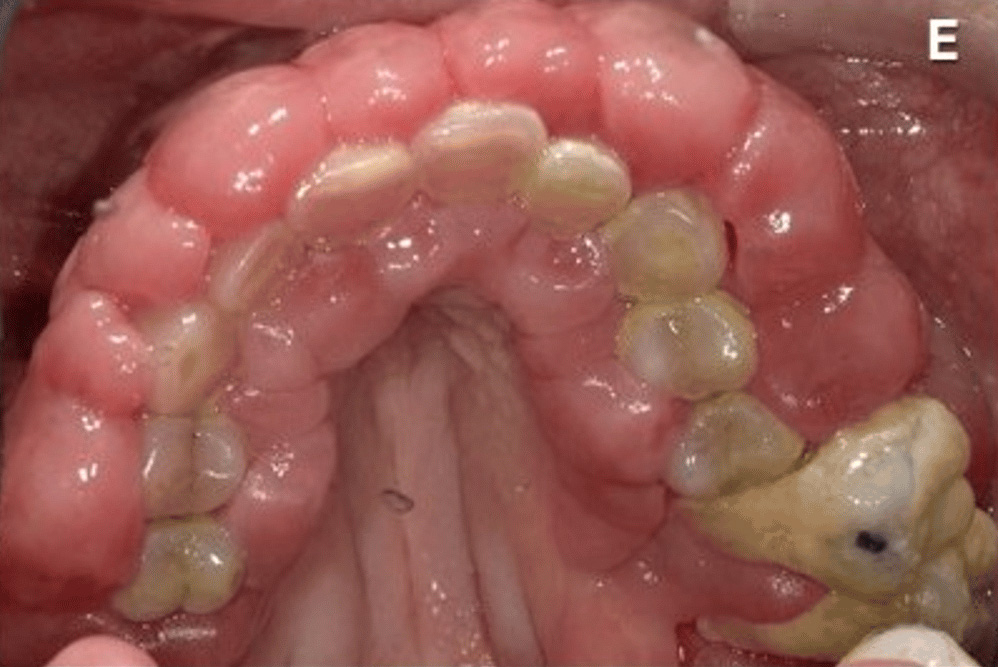

覚醒剤を乱用した61歳の男性の歯茎を撮影した画像。

5年間の覚醒剤使用とホームレス生活により口腔衛生不良があり、歯肉の肥大、疼痛、出血による咀嚼困難で病院へ。